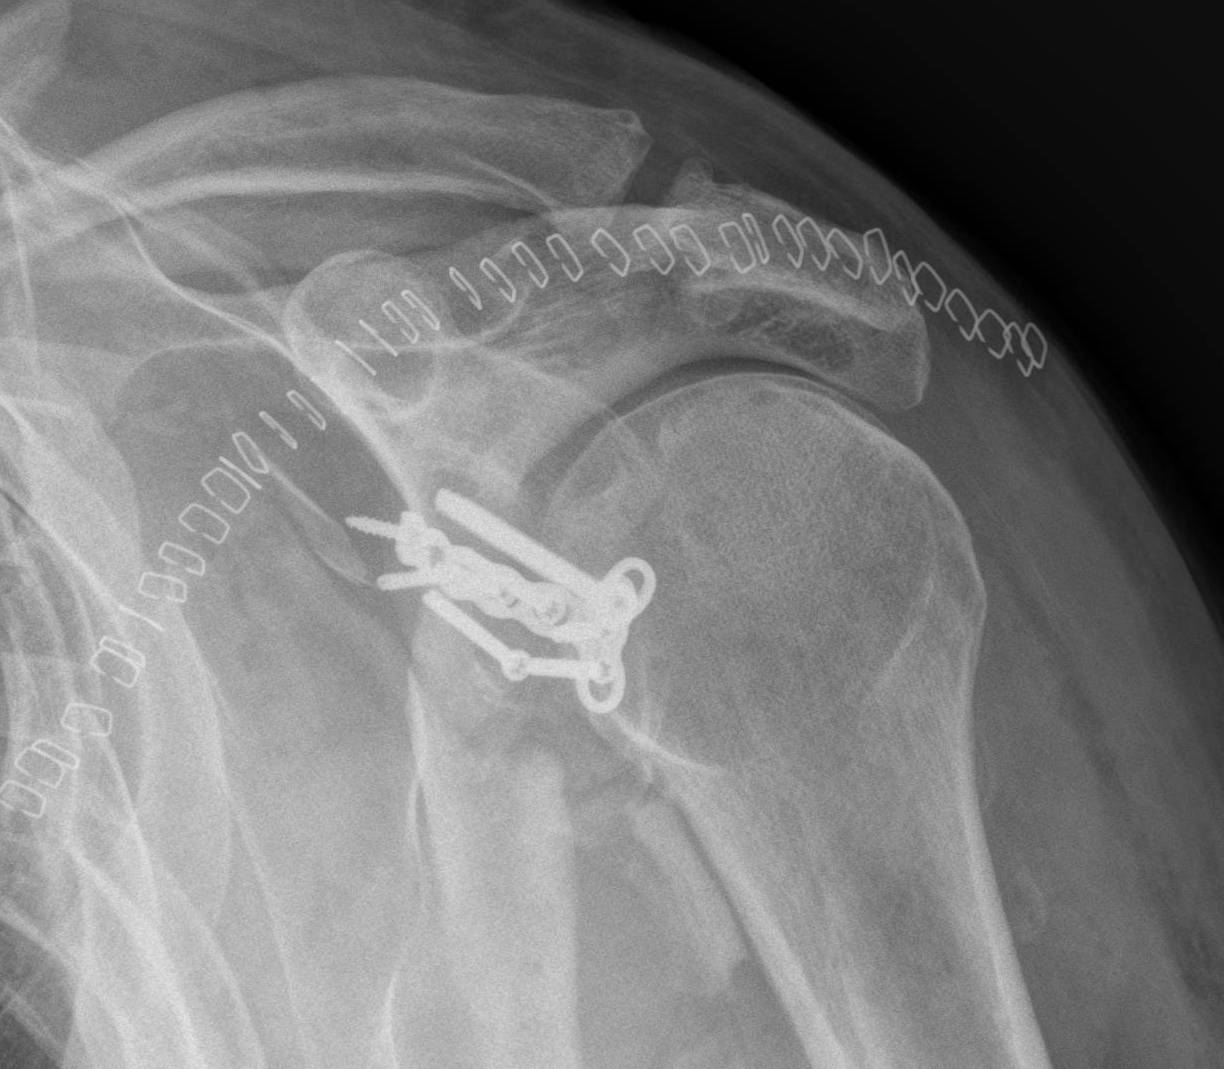

Case 1

Type I

Fractures of the Glenoid rim

I A anterior

I B posterior

Differentiate from small bony Bankart

- ORIF if > 1/4th or > 10 mm displaced (Neer)